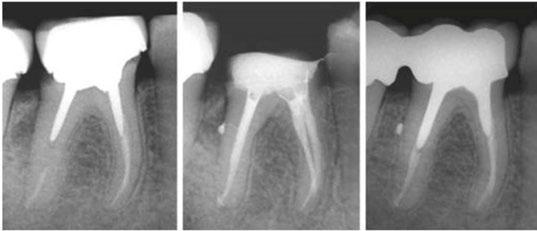

Figures 2-6: TrueTooth maxillary molar replica used from access to obturation and postendo restorative

4. Clear and opaque replicas are ideal for teaching mental imaging skills. Mental imaging is the most important skill a dentist brings to a root canal party, and while some of us have a natural ability in that regard, most of us need help figuring out how to do that. Training in clear replicas provides a view of exactly what is happening; for instance, when a rotary file is cutting through a curved canal, The best experience is to first do it in a clear replica and see it, then do the same procedure without directly seeing it in an opaque replica. Lots of “aha’s” happen with this teaching method. The results have been amazing (Figures 2-6).

accurate prediction because in 2017, after printing resolution got down to 0.016 mm, I was able to print the first extracted tooth replicas in both clear and opaque inks.

Since then, TrueTooth and TrueJaw replicas have been used worldwide, and of course, in my training lab in Santa Barbara. Here are a couple of things I’ve learned in the 8 years since their advent: